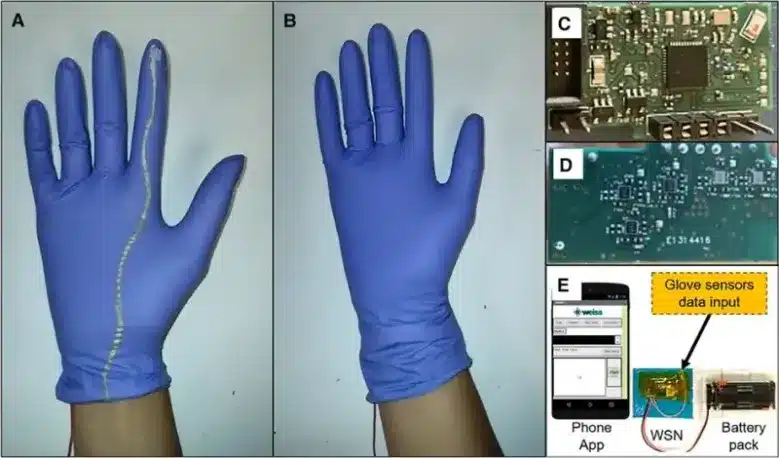

Οι ερευνητές ξεκίνησαν με ένα απλό χειρουργικό γάντι ως βάση για αυτή την τεχνολογία. Εκτύπωσαν εύκαμπτους αισθητήρες πίεσης και δύναμης στις άκρες των δακτύλων του γαντιού. Οι αισθητήρες αυτοί αποτελούνται από νανοσύνθετα μέταλλο-οξείδιο που μπορούν να παράγουν ηλεκτρικό ρεύμα όταν αγγίζουν ή τρίβονται πάνω σε αντικείμενα. Με έξυπνο τρόπο, οι ερευνητές εξασφάλισαν ότι οι αισθητήρες ήταν αρκετά λεπτοί ώστε να μην παρεμβαίνουν στην αίσθηση αφής του γιατρού. Ένα δεύτερο χειρουργικό γάντι μπορεί να φορεθεί πάνω από το γάντι της ομάδας, για να διατηρηθούν τα πράγματα αποστειρωμένα στην κολπική κοιλότητα. Οι ερευνητές ανέπτυξαν επίσης μια εφαρμογή για smartphone, η οποία επιτρέπει στους κλινικούς γιατρούς να βλέπουν τα δεδομένα των αισθητήρων σε πραγματικό χρόνο. Η παραγωγή κάθε γαντιού ανίχνευσης κοστίζει λιγότερο από 1 δολάριο.